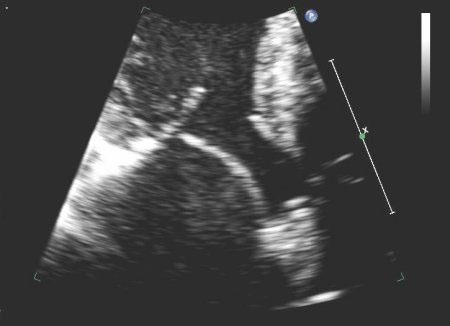

Mitral valve P2 leaflet prolapse: 3D view

From the collection of Prakash P. Punjabi

See this image in context in the following section/s: